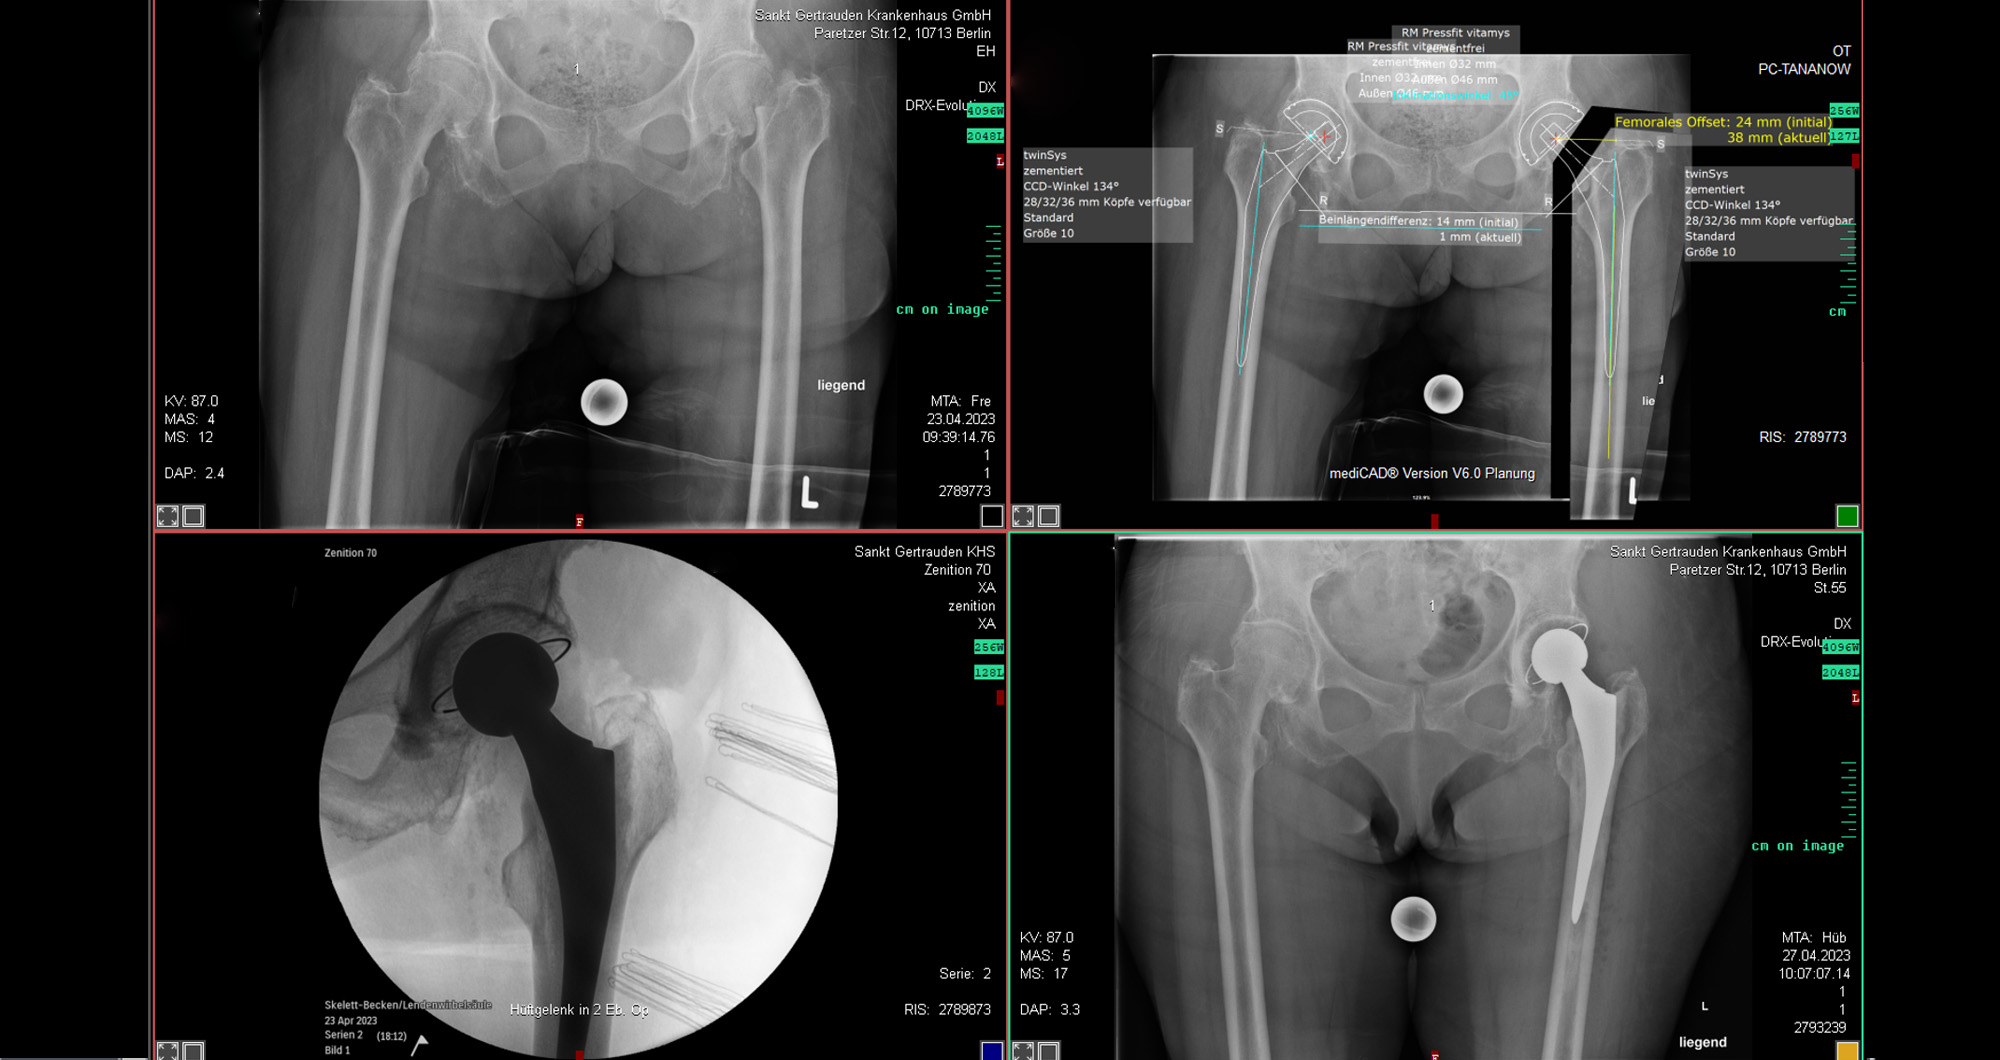

Von links oben in Uhrzeigerrichtung: 1.Mediale Schenkelhalsfraktur mittels Duokopfprothese 2. Mediale Schenkelhalsfraktur mittels Hüft-TEP in Hybrid-Technik (teilzementiert) 3. Mediale Schenkelhalsfraktur mit DHS inkl. Antirotationsschraube 4. Mediale Schenkelhalsfraktur mit Hüft-TEP zementiert 5. Laterale Schenkelhalsfraktur/pertrochantäre Femurfraktur mit Hüft-TEP durch Rekonstruktionsschaft zementfrei 6. Subtrochantäre Fraktur mit TFNA Lang inkl. Cerclage 7. Mediale Schenkelhalsfraktur mit einem kurzen Nagel bei pertrochantärer Fraktur